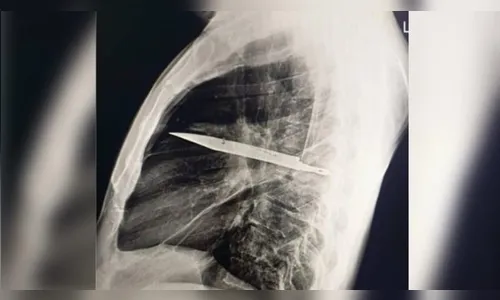

Surpresa no raio-x

O exame atual mostrou que uma lâmina estava presa ao lado direito do tórax, encostada à escápula. Apesar do tamanho, não atingiu órgãos vitais. Segundo os médicos, o acúmulo de pus foi causado pela presença do corpo estranho e por tecido danificado ao redor.